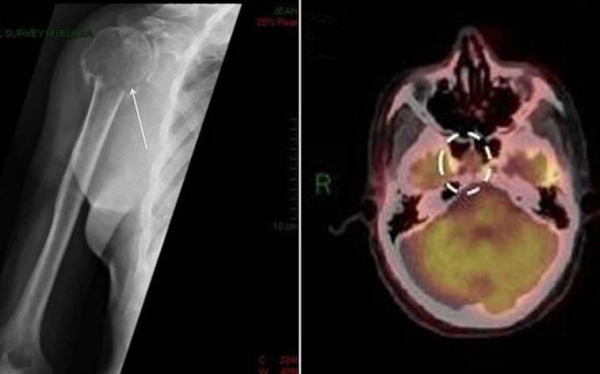

- Рентгенодиагностика. При костных болях назначается рентгенография грудной клетки, позвоночника и конечностей, с помощью которой определяются объемные новообразования. Для точной визуализации опухолей и определения степени распространенности процесса проводится КТ пораженной области тела. Методика ПЭТ-КТ показана для диагностики генерализованной плазмоцитомы.

Плазмоцитома глазницы как компонент миеломной болезни. У женщины 76 лет, в течение трех лет страдающей иммуноглобулин-С-лямбда множественной миеломой и получавшей химиотерапию, развился левосторонний экзофтальм. КТ, аксиальная проекция: та же пациентка, что и на рисунке выше; определяются диффузное объемное образование в височной части глазницы, смещение зрительного нерва в медиальную сторону, деструкция скуловой кости и прорастание опухоли в головной мозг и височную ямку. Микропрепарат новообразования, показанного на рисунке выше: отмечаются пласты атипичных плазматических клеток (гематоксилин-эозин, х75). Левосторонний экзофтальм и отек века у пациента 52 лет с диагностированной миеломной болезнью. Аксиальная Т1 -взвешенная МРТ с гадолиниевым усилением: тот же пациент, что и на рисунке выше. Видно крупное мягкотканное образование глазницы, поражающее слезную железу. Микропрепарат новообразования, показанного на рисунке выше: наблюдается злокачественная плазмоклеточная опухоль и митотическая активность (гематоксилин-эозин, х200).